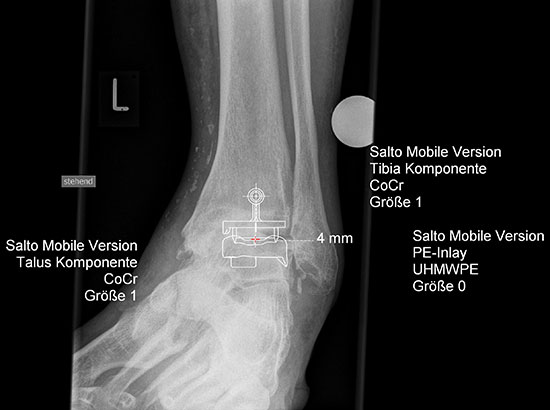

Endoprothesenversorgung des oberen Sprunggelenkes

Bei Destruktion der Gelenkflächen (LDE-Stadien 4 und 5) kommen am oberen Sprunggelenk (OSG) die endoprothetische Versorgung oder die Arthrodese (Cave: erhöhte Pseudarthrosenrate bei RA!) in Betracht. Die erfolgreiche Implantation einer Endoprothese am OSG setzt einen stabilen Bandapparat, eine gerade oder korrigierbare Bein- bzw. Rückfußachse, eine ausreichende Knochenqualität und eine nur moderate körperliche Belastung voraus, ansonsten sollte der Arthrodese der Vorzug gegeben werden. Bei korrekter Indikation weisen die beiden Verfahren hinsichtlich AOFAS (American Orthopedic Foot and Ankle Society) hindfoot score, Patientenzufriedenheit und Revisionsraten ähnliche Ergebnisse auf 4. Die 10-Jahres-Überlebensrate liegt für die modernen Sprunggelenksimplantate der zweiten Generation bei 70-90%. Die Prothesenversorgung ermöglicht Rheumapatienten mit einer im Durchschnitt niedrigeren physischen Belastung eine 8-10 jährige schmerzfreie Funktion 5.

Planung einer Prothesenversorgung am oberen Sprunggelenk.

Abbildung 6